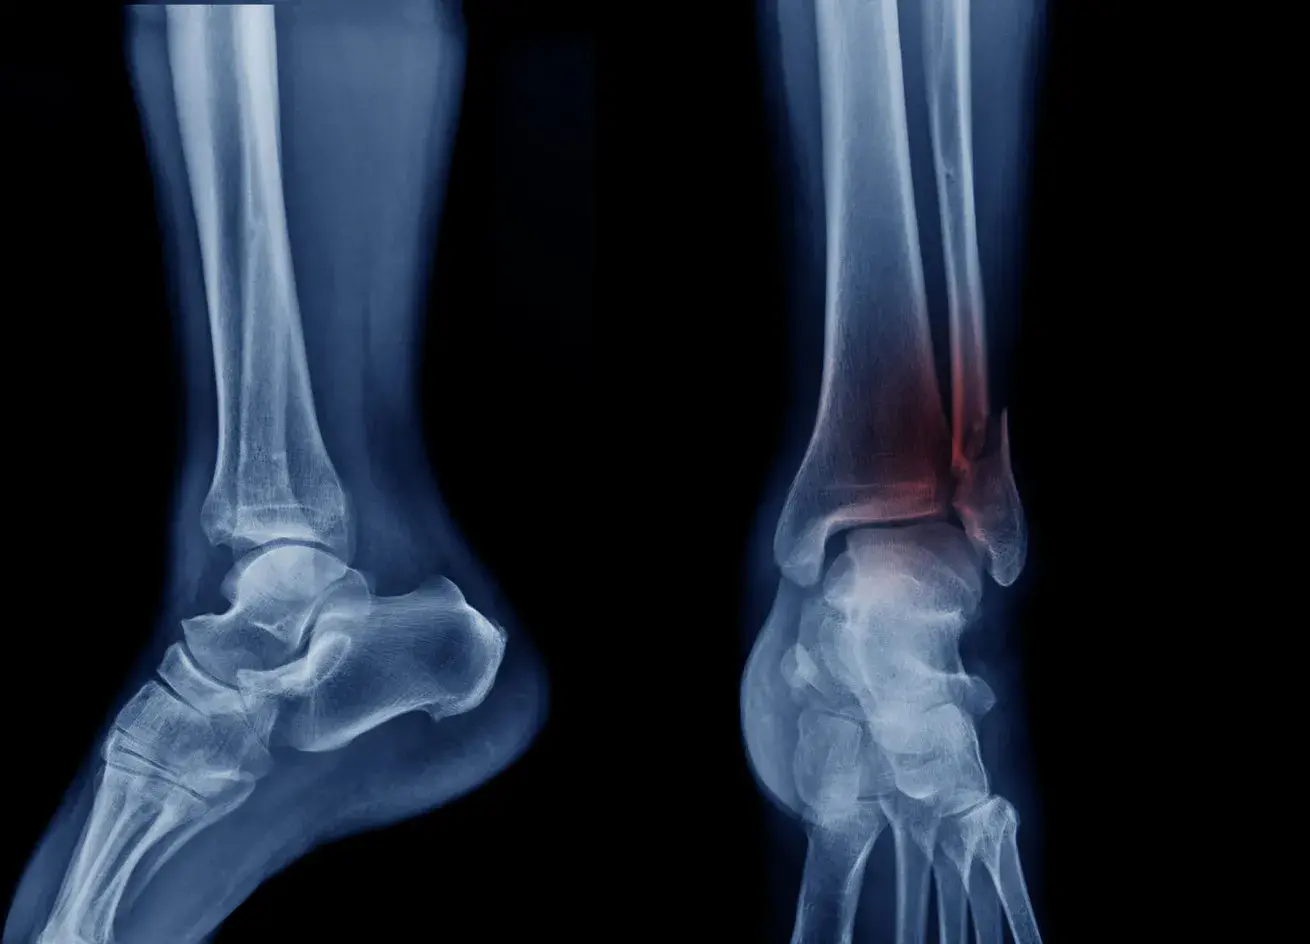

X-ray image of the ankle